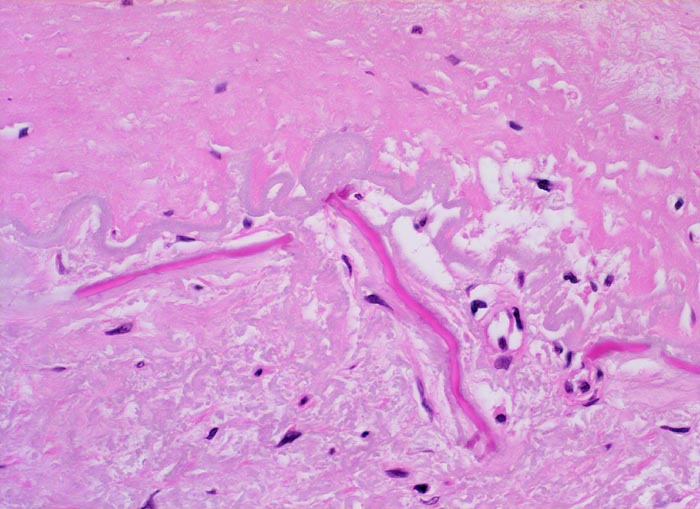

Die Atherosklerose befällt Arterien vom elastischen Typ und die grossen und mittelgrossen Arterien vom muskulären Typ. Die früheste Läsion, der Lipidstreifen, besteht aus einer fokalen Akkumulation von Lymphozyten und glatten Muskelzellen und von Serumlipoprotein in Makrophagen der Intima (> 5267). Zirkulierende Monozyten infiltrieren die Intima, nehmen alteriertes LDL Cholesterin auf und wandeln sich dadurch in Schaumzellen um. Diese Läsion kann sich durch zunehmende Lipidakkumulation und Migration sowie Proliferation von Myofibroblasten zum Präatherom mit wenig extrazellulären Lipidablagerungen und schliesslich zum Atherom (> 9003) mit zentral konfluierten extrazellulären Lipidmassen (> 9004) und nekrotischem Detritus weiterentwickeln. Die eingewanderten Mediamyozyten produzieren extrazelluläre Matrix, welche über dem Atheromkern aus extrazellulärem Lipid, Schaumzellen, Kalziumsalzen und Zellschutt eine fibröse Deckplatte bildet. Die atheromatöse Plaque kann narbig umgebaut werden, dystroph verkalken und konsolidieren oder zu einer komplizierten Plaque fortschreiten. Komplizierte Läsionen sind charakterisiert durch Ulzeration, Thrombose oder Plaqueeinblutungen. Bei einer Verletzung des Endothels oder einer Ruptur der fibrösen Deckplatte kommt der thrombogene Inhalt des Lipidkerns in Kontakt mit dem zirkulierenden Blut und es bildet sich eine Gefässthrombose. Wiederholte Rupturen mit nachfolgender Organisation der Thrombose vergrössern die Plaque und führen zu einer zunehmenden Gefässeinengung. Bei langsam gewachsenen schweren Stenosen bildet sich oftmals ein guter Kollateralkreislauf aus, welcher bei plötzlichem Gefässverschluss einen Infarkt im Versorgungsgebiet der verschlossenen Arterie verhindern kann. Grosse inter- und intraindividuelle Unterschiede bezüglich der relativen Anteile von weichen atheromatösen und derben fibrotischen bzw. verkalkten (> 4557) Bestandteilen der Plaques bestimmen wesentlich die Stabilität bzw. Vulnerabilität der Läsionen. Der Lipidanteil liegt bei rupturierten Plaques generell höher als bei Plaques mit intakter fibröser Deckplatte.

• Fibröse bindegewebige Deckplatte über dem Atheromkern

• Partielle Zerstörung der Lamina elastica interna.

• Atrophie der glatten Muskulatur der Media.